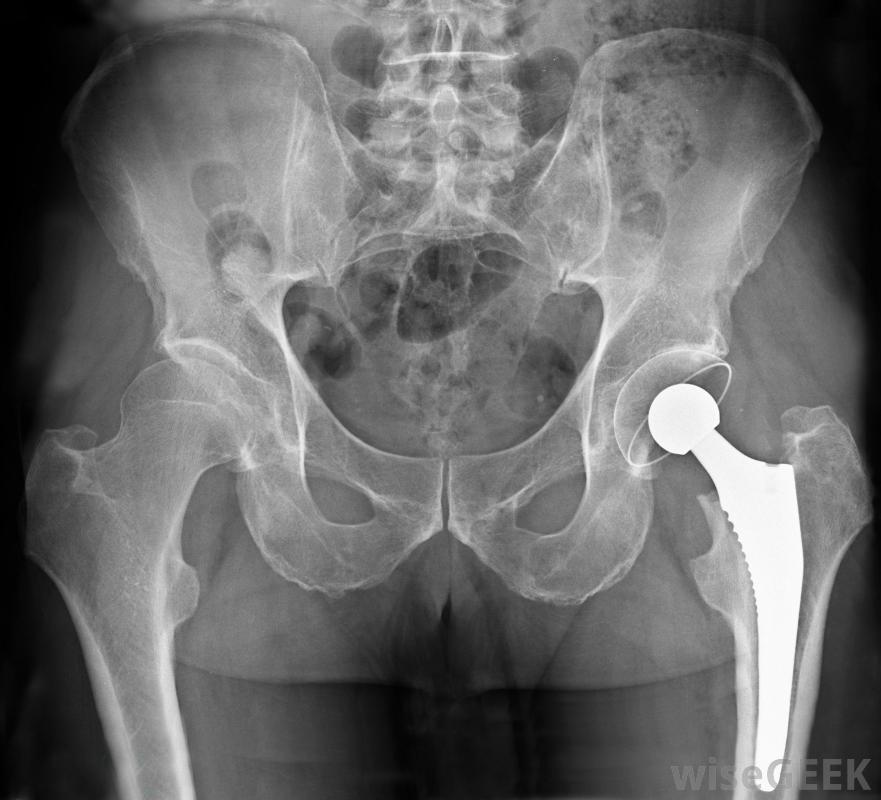

骨盆區域的X光片顯示金屬置換髖關節。